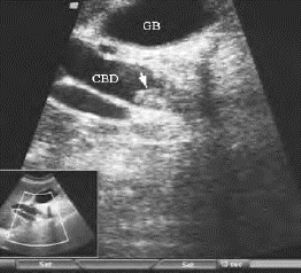

1.29第25章 胆管系统

1.29.1一、胆管系统的解剖

1.29.2二、检查方法

1.29.3三、正常超声表现